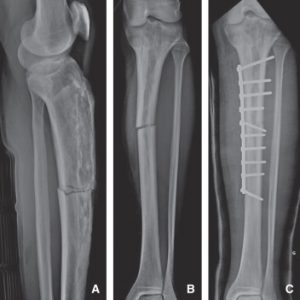

Quizá el nombre te suene. Quizá no tanto. Pero hoy debes conocer qué son las fracturas patológicas. Son ese tipo de fracturas que ocurren sobre un hueso que no está